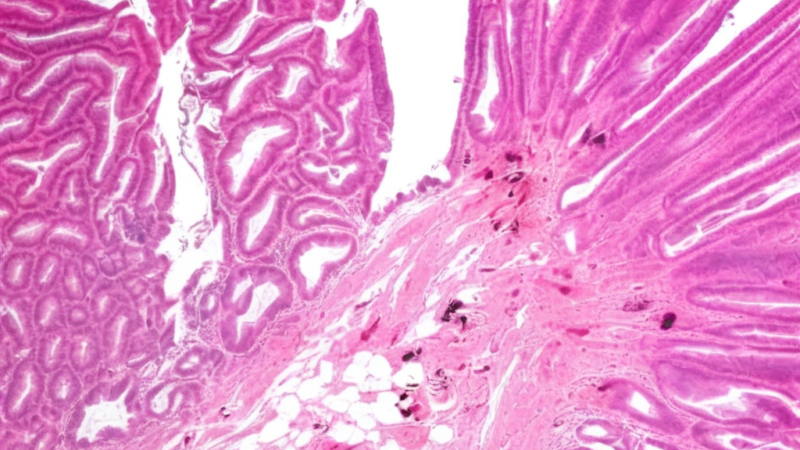

According to research from Karolinska Institutet in Sweden and NYU Grossman School of Medicine, published in Clinical Gastroenterology and Hepatology, not all precancerous colorectal lesions (called dysplasia) carry the same risk for people with IBD. This comprehensive registry study examined the long-term outcomes for IBD patients who developed these precancerous changes, revealing that the grade or severity of dysplasia significantly impacts future cancer risk.

The findings demonstrate that dysplasia grade serves as a crucial predictor of future colorectal cancer development, suggesting that current surveillance and treatment protocols might benefit from more nuanced, grade-specific approaches. This research represents a significant step forward in personalizing cancer prevention strategies for the IBD community.

The distinction between different grades of dysplasia is particularly significant because it suggests that not every precancerous finding should trigger the same level of concern or intervention. Low-grade dysplasia, while still requiring careful monitoring, may not carry the same urgent implications as high-grade changes. This nuanced understanding could help reduce anxiety for patients whose surveillance colonoscopies reveal lower-risk precancerous changes, while ensuring that those with higher-risk findings receive appropriately intensive management.

The study also highlights the importance of consistent, high-quality surveillance colonoscopy in IBD care. The ability to detect and grade dysplasia accurately becomes even more critical when we understand that these grades carry different prognostic significance. This underscores the value of working with gastroenterologists who have specific expertise in IBD and access to advanced endoscopic techniques.